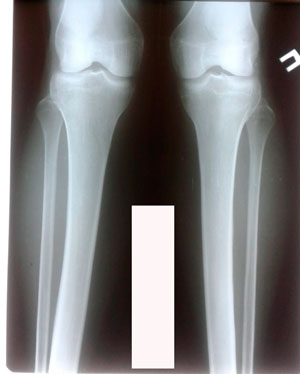

Исходник - 28 лет.

Дата операции - 03.01.2020.

перед крутками

IMG_8213-13-01-20-12-54.JPG

Дата снятия аппаратов - 27.03.2020

Срок сращения - 87 дней.